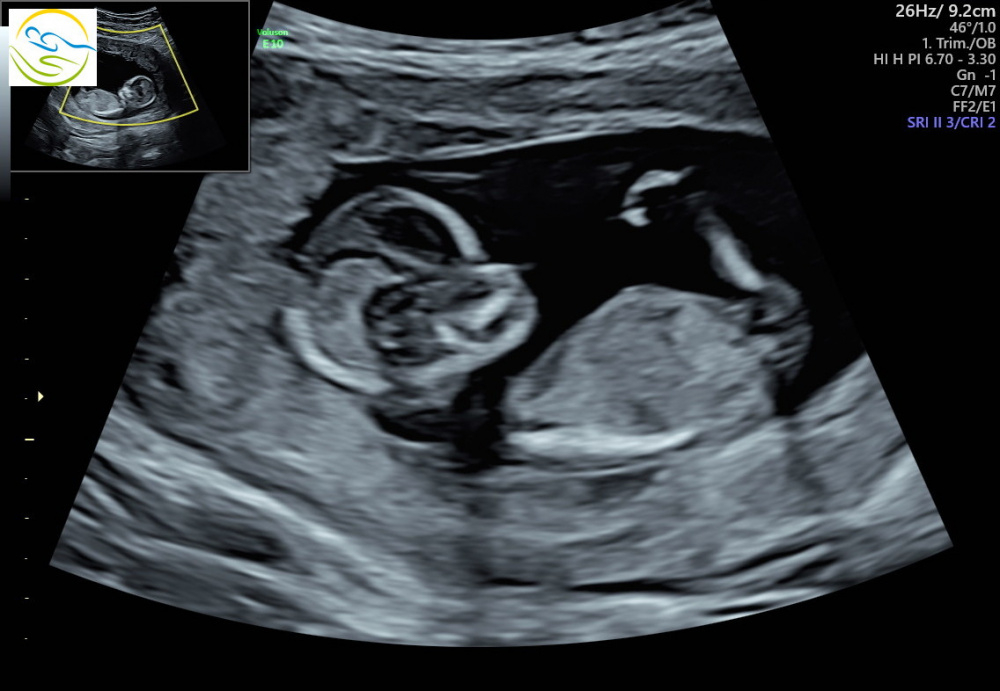

Das bild ist von meinem ersttrimesterscreening, da war ich gerade frisch und der 15.ssw, leider wollte mir die Ärztin auch keine tedenz sagen, jedoch hat sie einmal das Baby "sie" genannt, war vl aber auch einfach nur so. Meine Schwester meint auch ein Mädchen zu erkennen, ich erkenne aber nichts haha, was meint ihr? Am Donnerstag bin ich wieder beim FA und erfahre dann hoffentlich das Geschlecht

Mich würde sehr interessieren ob ihr was erkennen könnt. Unsere fa meinte sehr wahrscheinlich ein junge, was mich allerdings etwas skeptisch macht ist die nabelschnur davor . Würde mich sehr über antworten freuen